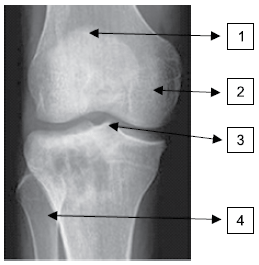

As estruturas assinaladas correspondem a qual alternativa?